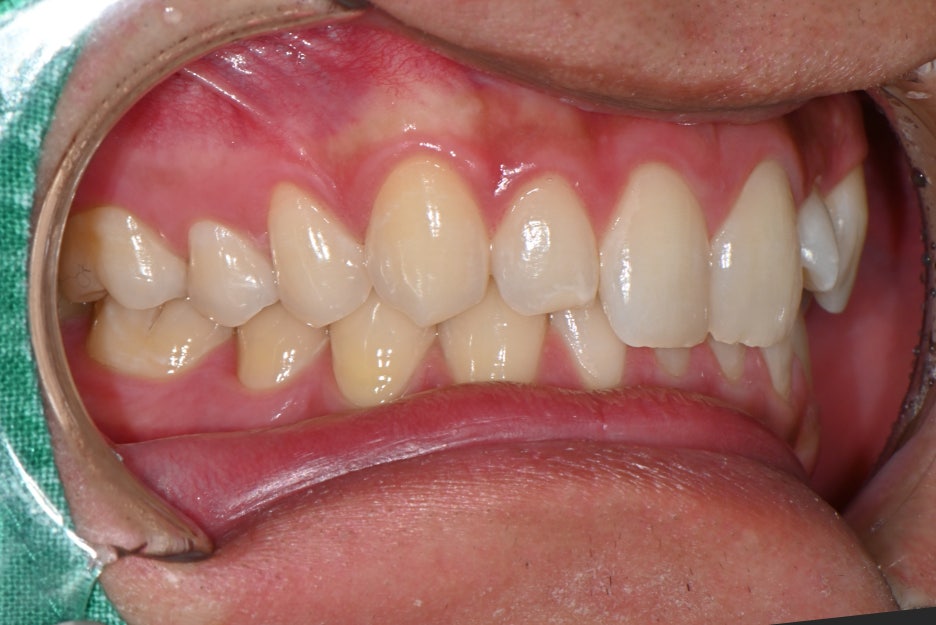

특히 양쪽 앞니 옆에 위치한 작은 치아가

선천적으로 작아 보이는 형태였고,

색도 맞지 않아 전체적으로 웃을 때

인상이 흐려지는 상태였습니다.

1.앞니 옆 치아가 작게 나 있는 형태

사람마다 치아 크기와 형태는 다르지만,

양쪽 균형이 크게 다르면 밝기를 높여도

자연스러움이 나오기 어렵습니다.